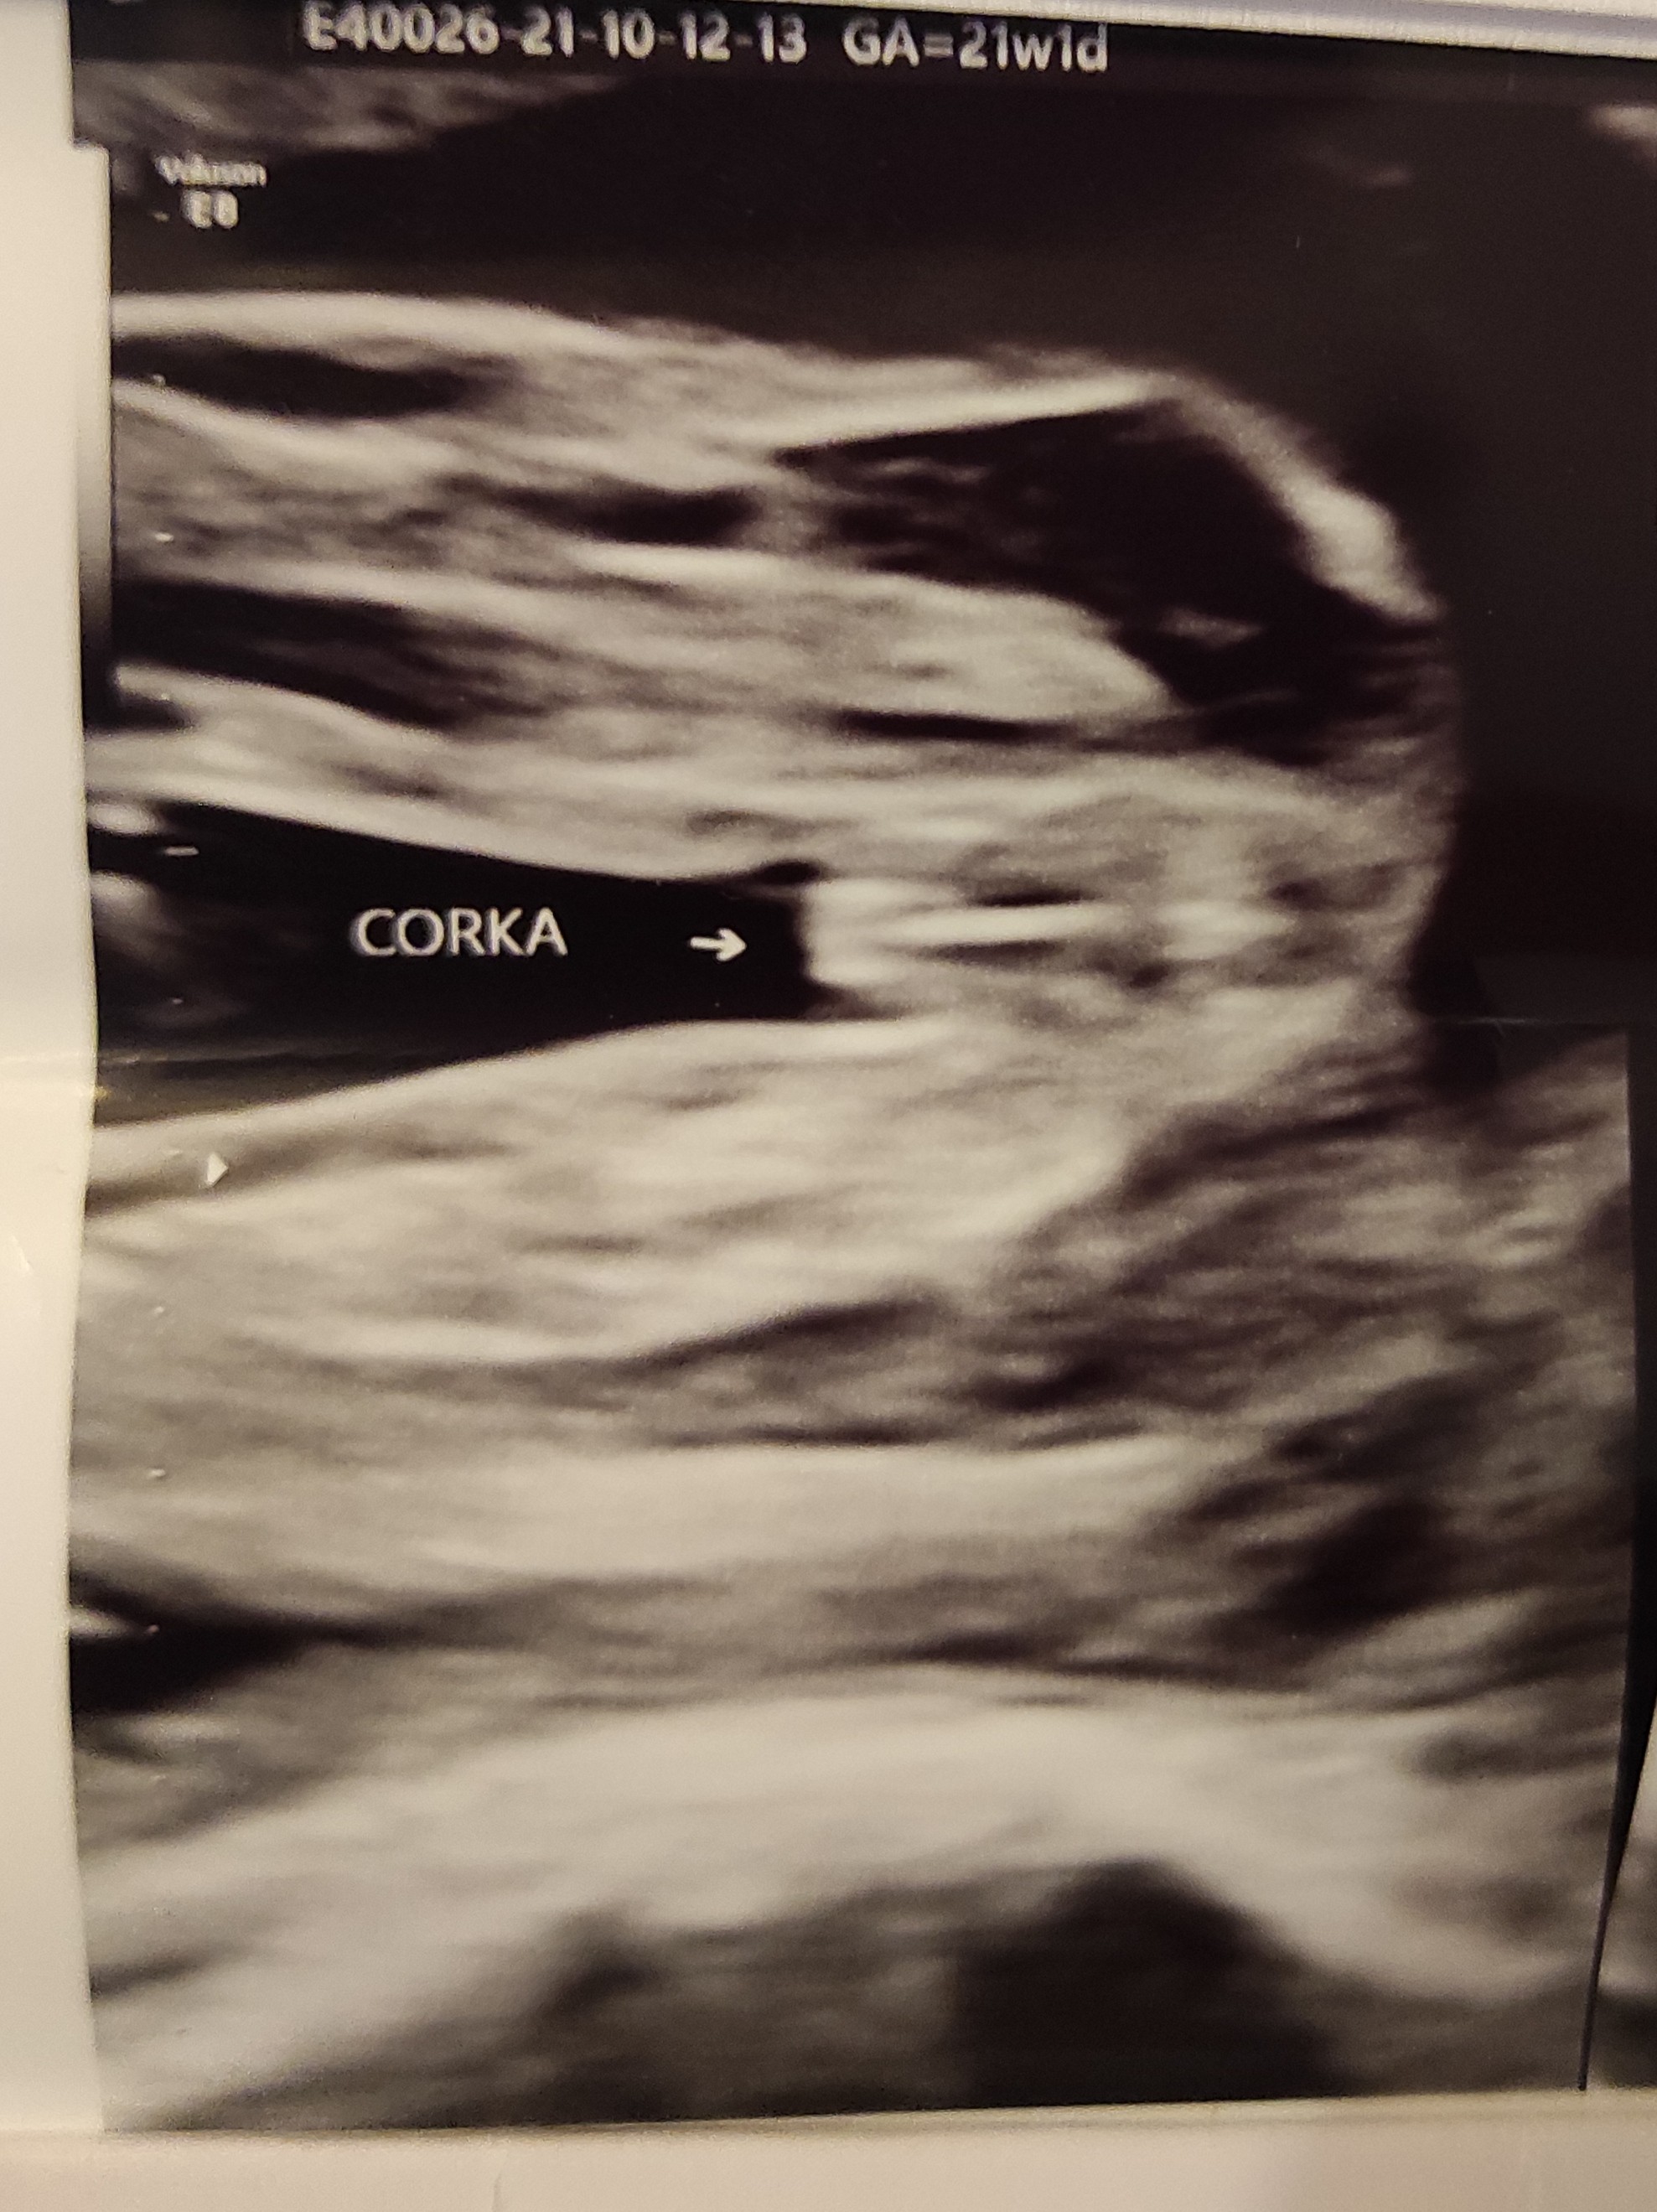

Na tym etapie ciąży raczej płeć jest pewna - przy dobrym lekarzu i usg jest naprawdę nikła możliwość pomylki. A tu chłopak jest ewidentnie, pięknie się pokazał![]()

Zdjęcie definiujące płec wygląda inaczej.. któraś z mam wczęściej wrzucałaHej, u mnie 21 TC lekarz stwierdził na wcześniejszej wizycie że chłopczyk a teraz dziewczynka. Czy to możliwe? Jak sądzicie po USG?